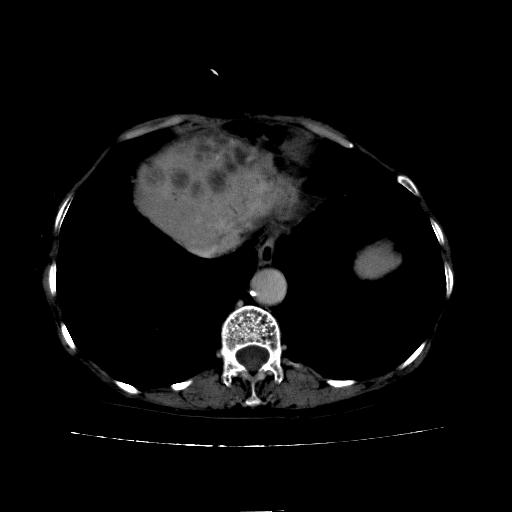

患者08年胆囊结石切除,之前没有做过ct,现在患者厌食。

平扫

看片子胆管里结石,肝上显示的占位会不会是胆管癌?大家帮忙看看,图像不太好,手头的处理文件没有,大致转换了一下,有原始图像数据